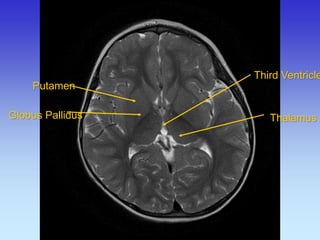

Putamen

Globus Pallidus

Third Ventricle

Thalamus